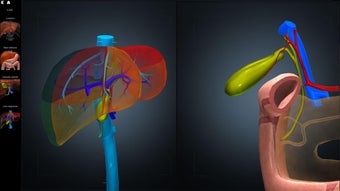

Anatomy Learning - 3D Atlas è un'app gratuita per Android che appartiene alla categoria Medicina ed è stata sviluppata da AnatomyLearning. È consigliata per principianti, studenti di medicina, apprendisti visivi, professionisti medici, medici.

Questa app è meglio conosciuta per le seguenti caratteristiche e qualità: strumento di studio, apprendimento dell'anatomia, strumento di apprendimento e riferimento di base.